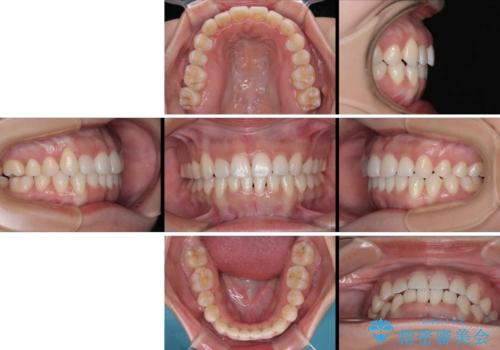

- 20代女性

- クリアブラケット

- 1年3ヶ月

- 10-30回